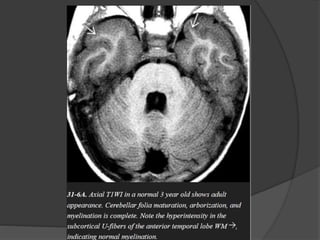

 Normal myelination… Hyperintense on T1 &

Hypointense on T2.

 T1W parallel increase in lipids while T2W

correlates to the period of maturation of myelin

sheath.

General rules of myelination

 Caudad to cephalad.

 Central to peripheral.

 Posterior to anterior.

 Dorsal medulla / mid brain.

 Inferior / superior cerebellar peduncles.

 Posterior limb of internal capsule.

 Ventrolateral thalamus.

One month

 Deep cerebellar white matter.

 Corticospinal tract.

 Pre / post central gyri.

 Optic nerve / tracts.

Three month

 Cerebellar folia.

 Ventral brainstem.

 Optic radiation.

 Anterior limb of internal capsule.

 Occipital subcortical U fibers.

 Corpus callosum splenium.

Six month

 Corpus callosum genu.

 Paracentral subcortical U fibers.

 Centrum semioval ( Partial ).

Eight month

 Centrum semiovale ( complete except

frontoteporal area ).

 Subcortical U fibers ( complete except most

rostral frontal area ).

Eighteen month

 Essentially like adult.